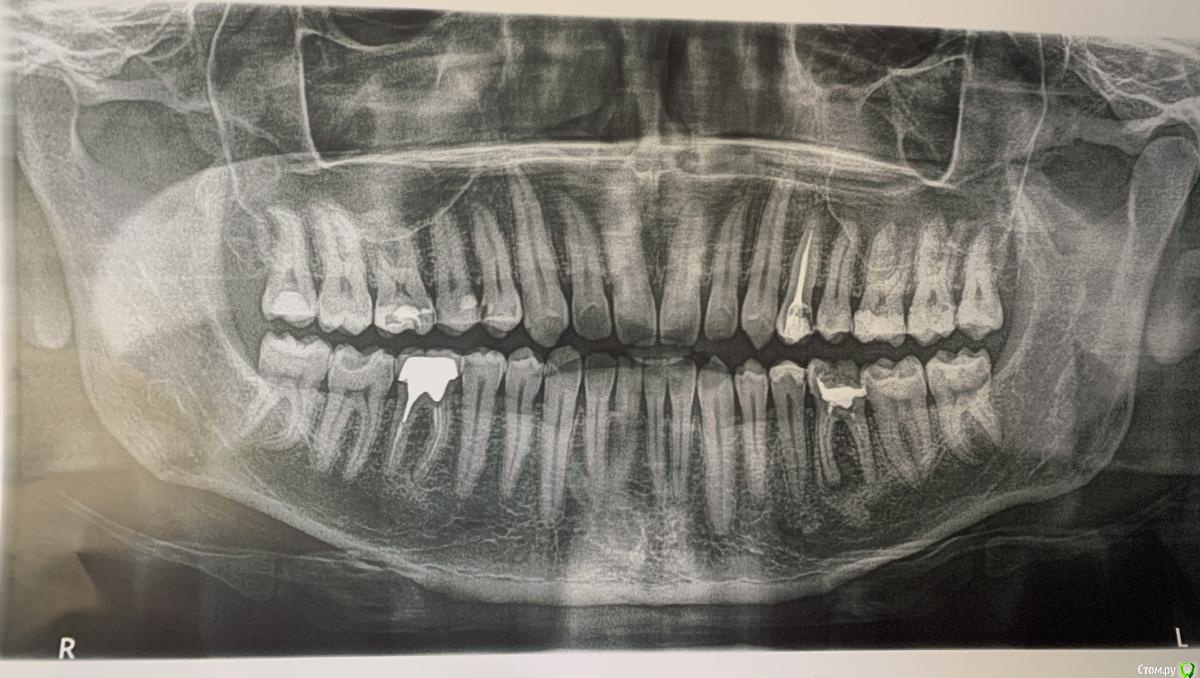

lodo4nik Опубликовано 7 июля, 2020 Поделиться Опубликовано 7 июля, 2020 Добрый день! Прошу помочь с решением судьбы зуба.На панорамном снимке мой стоматолог обнаружил новообразование в районе 36 зуба. Говорит причина в плохо залеченном канале-не вычистили все до конца при лечении.Этот зуб лечил около 10-15 лет назад (сейчас мне 35) в городской гос. поликлинике. Жалоб на него никаких нет и не было-не болит, не реагирует на холодное/горячее, выделений в районе зуба нет.Для уточнения сделали точечный рентген.Мой стоматолог советует зуб удалять и через пол года ставить имплант-т.к. будем сохранять зуб-сохраним новообразование. Сейчас это доброкачественное образование, которое со временем может перерасти в злокачественное. Во втором медцентре-хирург однозначно сказал удалять.В третьем медцентре сказали, что зуб можно спасти, но для уточнения отправили на КЛКТ. Посмотрели и сказали, что это киста и она уже очень разрослась-зуб под удаление, не спасти.Отправил снимки в четвертый медцентр, в столице (сам я живу в областном центре), знакомый посоветовал их-сказал что сохранили зуб, когда все остальные врачи настаивали на удалении. Оттуда пришел ответ-приезжайте, перепломбируем каналы, сохраним зуб. Но они КЛКТ не смотрели.Я в растеряности-что делать. Помогите окончательно определиться.И еще дополнительный вопрос. У меня повышен С реактивный белок высокочувствительный последние лет 8, не значительно, но постоянно 1.5-2.5 (референс <1) . Причина может быть в этом зубе?Ссылка на КЛКТ:https://yadi.sk/d/bVoEJ3dM53D3CAАрхив с КЛКТ:https://yadi.sk/d/YkVkCMyxDQsXQAФото без сжатия:https://yadi.sk/d/_LrW1Gt7YADgFQЗаранее спасибо! Ссылка на комментарий

red_butler Опубликовано 9 июля, 2020 Поделиться Опубликовано 9 июля, 2020 Я в растеряности-что делать. Помогите окончательно определиться. Здравствуйте, новообразования нет, это банальный периодонтит, для принятия решения нужно очно или по фотографии оценить оставшийся объем твердых тканей, если зуб возможно восстановить, то повторное лечение корневых каналов, если нет, то удаление 2 Ссылка на комментарий